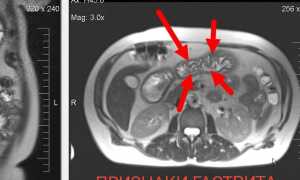

| КТ и МРТ с контрастированием | Исключает опухолевую природу дуоденита |